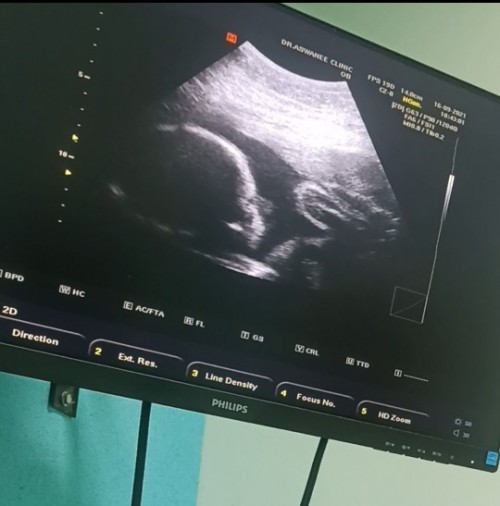

31+5แล้วค่ะ ลูกสาวค่ะ

ผู้หญิงค่ะ กำหนด15มีนา🥰

ซาวด์ตอน27weekจ้า ผู้ชาย_จ้า